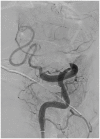

In this review article, we summarized the current advances in rescue management for reperfusion therapy of acute ischemic stroke from large vessel occlusion due to underlying intracranial atherosclerotic stenosis (ICAS). It is estimated that 24-47% of patients with acute vertebrobasilar artery occlusion have underlying ICAS and superimposed in situ thrombosis. These patients have been found to have longer procedure times, lower recanalization rates, higher rates of reocclusion and lower rates of favorable outcomes than patients with embolic occlusion. Here, we discuss the most recent literature regarding the use of glycoprotein IIb/IIIa inhibitors, angioplasty alone, or angioplasty with stenting for rescue therapy in the setting of failed recanalization or instant/imminent reocclusion during thrombectomy. We also present a case of rescue therapy post intravenous tPA and thrombectomy with intra-arterial tirofiban and balloon angioplasty followed by oral dual antiplatelet therapy in a patient with dominant vertebral artery occlusion due to ICAS. Based on the available literature data, we conclude that glycoprotein IIb/IIIa is a reasonably safe and effective rescue therapy for patients who have had a failed thrombectomy or have residual severe intracranial stenosis. Balloon angioplasty and/or stenting may be helpful as a rescue treatment for patients who have had a failed thrombectomy or are at risk of reocclusion. The effectiveness of immediate stenting for residual stenosis after successful thrombectomy is still uncertain. Rescue therapy does not appear to increase the risk of sICH. Randomized controlled trials are warranted to prove the efficacy of rescue therapy.